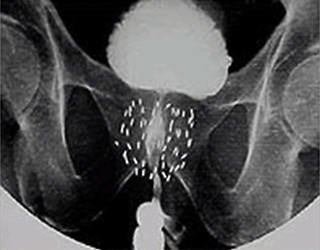

小さな線源を前立腺内に挿入し、前立腺内のがん病巣へ線源から放射線を照射する放射線治療です。

放射線治療の場合、がんのある前立腺のみに照射したいのですが、前立腺は上に膀胱、後ろに直腸が接しているため、従来の外部照射療法では前立腺だけでなく周辺の臓器にも多くの線量の放射線がかかってしまい、また密封小線源治療(シード治療)でもある程度の線量がかかってしまい、かかったところに有害事象(副作用)が出現していました。

前立腺への総線量72Gy > 直腸の耐容線量60Gy

放射線の影響は距離が離れれば低減します。そのため、当院では前立腺と直腸の間にゲル状の物質を挿入し、前立腺と直腸の間を1.0~1.5cm離すことで直腸被曝を低減させる処置として、『直腸周囲ハイドロゲルスペーサ・SpaceOAR®』の留置を行っています。

留置により放射線の直腸への影響が低減され、合併症が減ると考えられます。